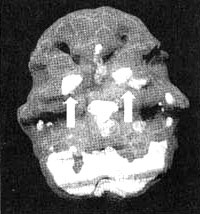

Система базальных ганглиев

Иллюстрация к книге — Измените свой мозг - изменится и жизнь! [i_036.jpg]

Трехмерное изображение — активный мозг, вид снизу.

Базальные ганглии — это комплекс крупных образований, расположенных в центральной части мозга окружающих центральную лимбическую систему.